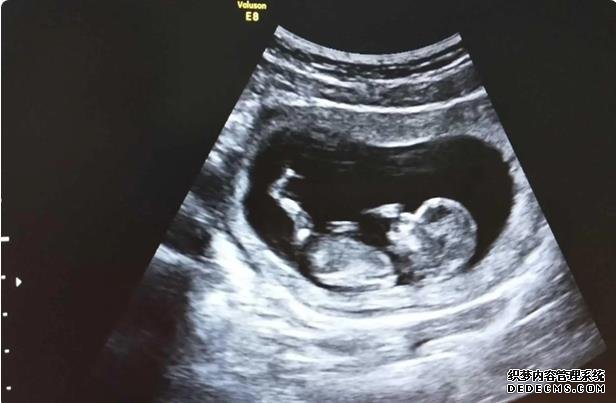

在胚胎移植后的14天,女方需要去医院进行血液HCG检测,以确定移植胚胎是否着床,即是否怀孕,如果怀孕,就需要做B超检查,这部分的费用以医院收费为准。

已有龙凤胎儿女一岁10个月,最近两天一直胃酸加上月经推迟10多天,去检查果然还是有了,怀孕6+了,B超已经有胎心胎芽了,和老公在一起8年没有自怀过,这次真的不敢相信自怀了,第一反应就是不能要,可是想想自己以前为了要孩子吃中药做检查做试管受了好多苦,这个就这样悄悄来了,我真的不想放弃,可是觉得养孩子真的很辛苦,到底该怎么办啊

实际上孕妇长时间保持一个姿势,无论是站着还是躺着,胎儿都不会喜欢,孕妇可以根据实际情况来调整自己的姿势,可以每隔一段时间就调整一下姿势,这样是有利于胎儿发育的,注意尽量不要长期保持一个姿势不动。孕妇在日常生活中要注意休息,同时也要注意运动,长时间的卧床和久站都是不好的,要注意劳逸结合,这样才能维持良好的胎盘血供。